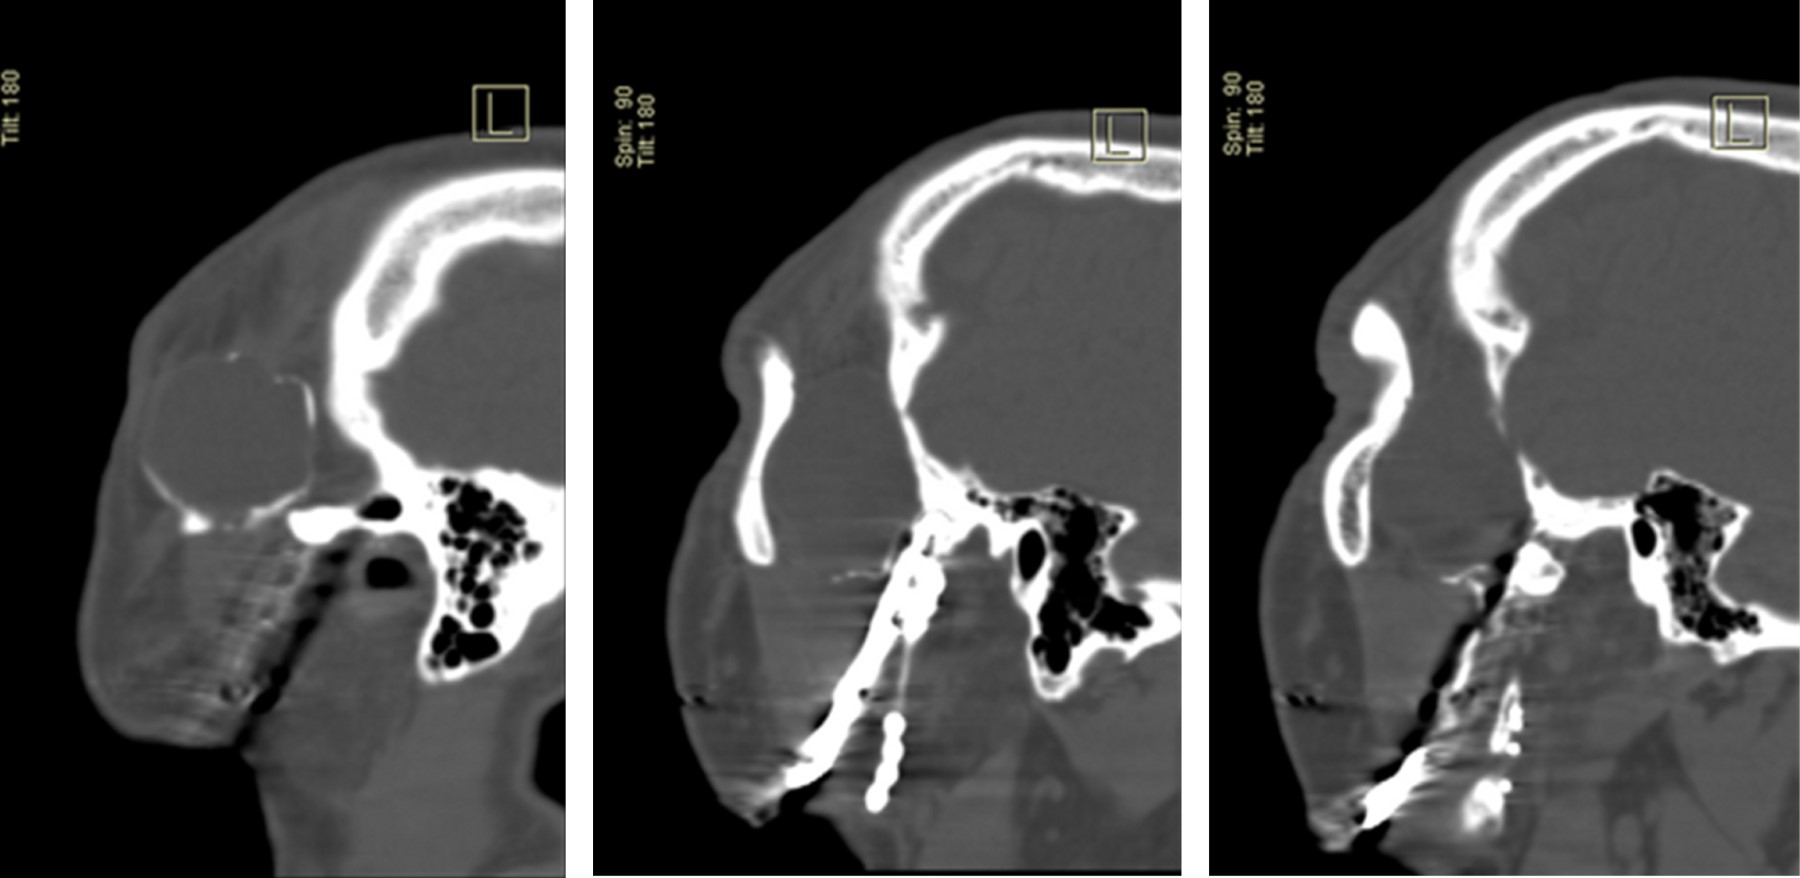

Se evaluó una tomografía computarizada (TC) de cabeza, una imagen isodensa en región de fosa temporal derecha, en la cual se observa infiltrando músculo temporal, extendiéndose a región de ATM derecha. Causando erosión de cortical del arco cigomático (Figura 2). Donde se evidencia imagen hiperdensa la cual se extiende imitando el contorno mandibular derecho hasta región de parasínfisis mandibular izquierda. Compatible con material de osteosíntesis de reconstrucción mandibular por el defecto óseo postresección de cuerpo, para sínfisis y rama mandibular derecha (Figura 3).

Figura 3